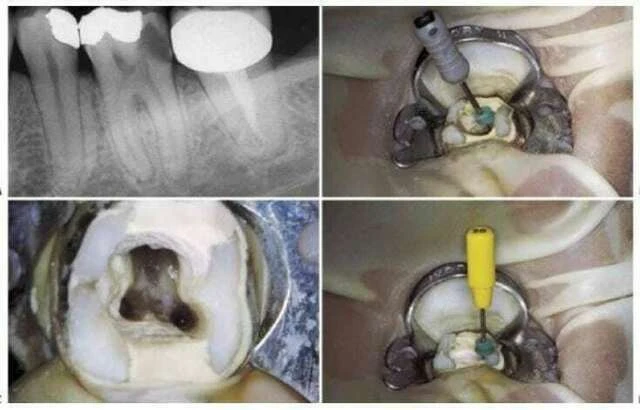

5. Nếu khó tìm thấy ống tủy, không nên dùng đê cao su cho đến khi tìm được miệng ống tủy, cũng như trường hợp răng mọc lệch, chen chúc hoặc bị răng giả che hay những trường hợp ống tủy bị canxi hóa. Hình dạng và độ nghiêng của những răng gần đó, mô nướu và những cấu trúc mô cứng bao xung quanh chân răng cũng có thể giúp ích trong việc xác định những ống tủy chân răng. Khi đã mở xoang tủy và xác định được ống tủy, có thể đặt đê cao su (hình 3.15).

Hình 3.15. A. Phim răng cối lớn 1 hàm trên, chân răng gần ngoài bị cắt vì lý do nha chu. B. Mở lối vào ống tủy, tháo đê cao su để clamp không gây trở ngại cho việc chụp phim kiểm tra lỗ vào ống tủy. C. Dùng file 06 ở chân xa ngoài sau khi chân trong đã được tìm thấy, làm sạch và tạo hình. Nên tháo đê cao su để tiện cho việc kiểm tra ống tủy. Cán dụng cụ nên buộc vào chỉ nha khoa và buộc đầu chỉ còn lại bên ngoài. D. Đặt lại đê cao su và hoàn thành việc điều trị theo cách truyền thống. E. Phim sau điều trị. F. Sau 4 năm.